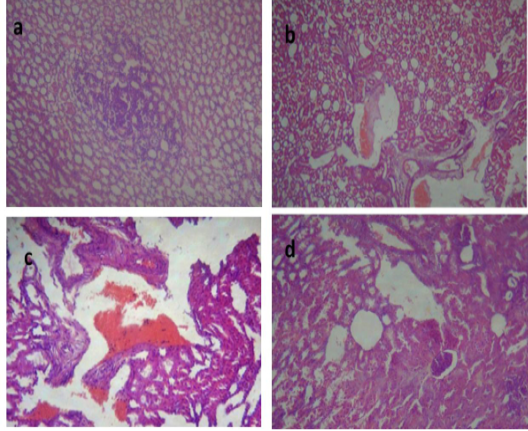

Liver of group (II) showing congested central vein and dilated hepatic sinusoids (a) (H&E ×400). Liver of group (III) showing severe congestion of the central veins (b). Cholangitis represented thickening of the bile duct wall by vascular congestion, edema and leukocytic infiltration besides cholestasis (c) (H&E ×100).Vacuolation of the hepatocytes (d) (H&E ×400).Liver of group (IV) showing interstitial hemorrhage and normal tissue architecture (e) (H&E ×520).